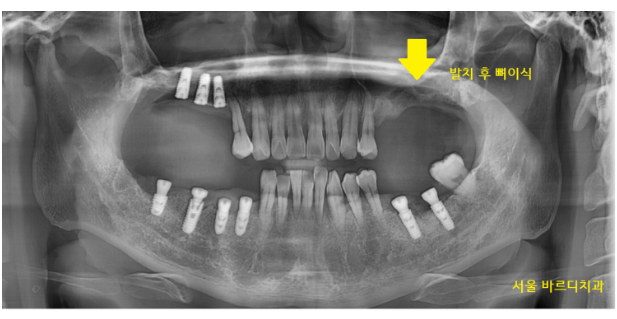

230703

잇몸뼈가 많이 없어 뼈를 많이 만들어야하는

윗니 어금니의 경우

발치 후 뼈이식을 하여 뼈가 만들어지길 기다리다

임플란트를 심기도 하였습니다.

231218

임플란트 뼈이식 흡연을 하시기 때문에

충분히 기다렸습니다.

5월달에 왼쪽 위부터 수술했는데

7개월정도 지나 보철을 올려드렸어요.